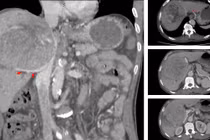

Hành trình giành sự sống cho người bệnh ung thư gan 'tiên lượng 9 tháng'